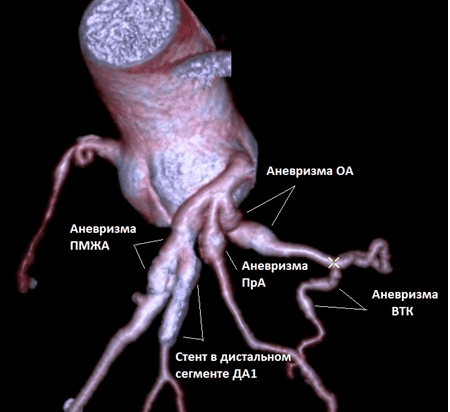

При коронароангиографии были выявлены множественные АКА: в проксимальном сегменте ОА, в проксимальном сегменте ПМЖВ, проксимальном сегменте промежуточной ветви ЛКА и в проксимальном сегменте ветви тупого края (ВТК). Кроме того, в устье 1 диагональной артерии (ДА), которое тоже имело небольшое аневризматическое расширение, была выявлена тромботическая окклюзия (рис. 2 и 4). Пациенту была выполнена реканализация коронарным проводником PT2 MC, который был доставлен в дистальный участок артерии. По коронарному проводнику заведен аспирационный катетер Export Advance. Выполнена тромбоаспирация с получением тромботические масс из 1 ДА и установлен стент с лекарственным покрытием Promus Element Plus 3,5×28 мм. При контрольной коронароангиографии кровоток в месте установки стента удовлетворительный (рис. 3), участков резидуального стеноза и диссекции не выявлено. На ЭКГ, зарегистрированной после чрескожного коронарного вмешательства, отмечалась ускоренная динамика проникающего инфаркта миокарда в области передней и боковой стенок левого желудочка. На фоне проводимой консервативной терапии состояние пациента улучшилось, и он был направлен на медицинскую реабилитацию в санаторий с последующим освидетельствованием для определения категории годности к военной службе.